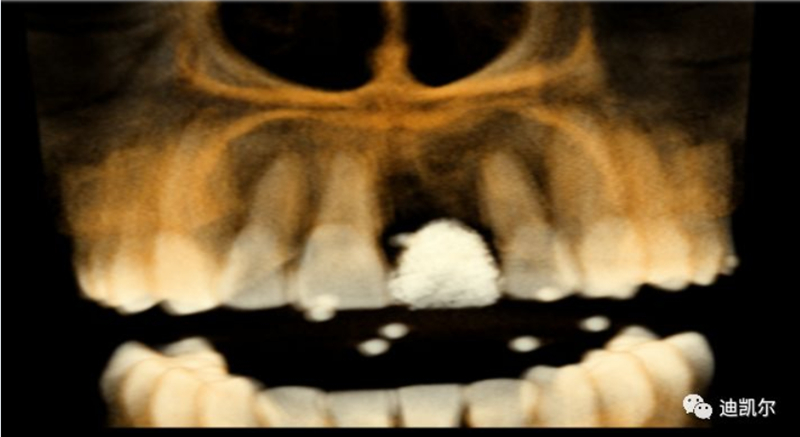

術(shù)前CBCT圖像和測量數(shù)據(jù)

*CBCT顯示骨缺損嚴重,種植窩洞制備困難,種植體很難獲得初期穩(wěn)定性